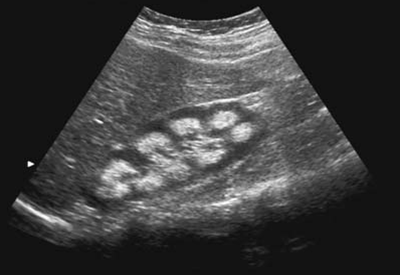

Feline Enlarged Kidney - Clinician's Brief

The right kidney is moderately enlarged, slightly irregular, and nonpainful on palpation. Chronic pyelonephritis and systemic fungal dis-ease are other differentials causing a pyogranu-lomatous response in the kidney; when present, ... Get Doc